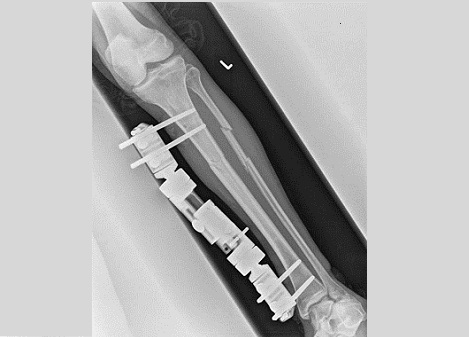

Fig8. - Open tibia fracture.

Fig8. - Treated with a monolateral external fixator.